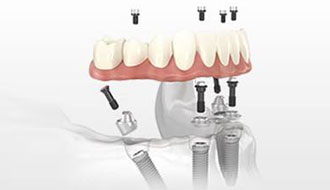

精研项目: 擅长前牙美学种植、微创种植牙、即拔即种的种植与修复、单颗及多颗牙缺失种植、ALL-on-4/6半口及全口无牙颌种植修复...

精研项目: All-on-4、All-on-6全口种植,上颌窦提升术,GBR骨再生引导术,前牙美学区种植及修复技术,即刻种植即刻修复技术...

精研项目: 擅长口腔数字化舒适种植、单颗、多颗种植,全口、半口疑难种植牙的无痛即刻种植及美学修复,精通各类上颌窦内/外提升术...

精研项目: 口腔微创种植、微创即刻负重种植、前牙美学即刻种植、种植美学修复技术,牙槽外科各种疑难复杂牙拔除手术等等...